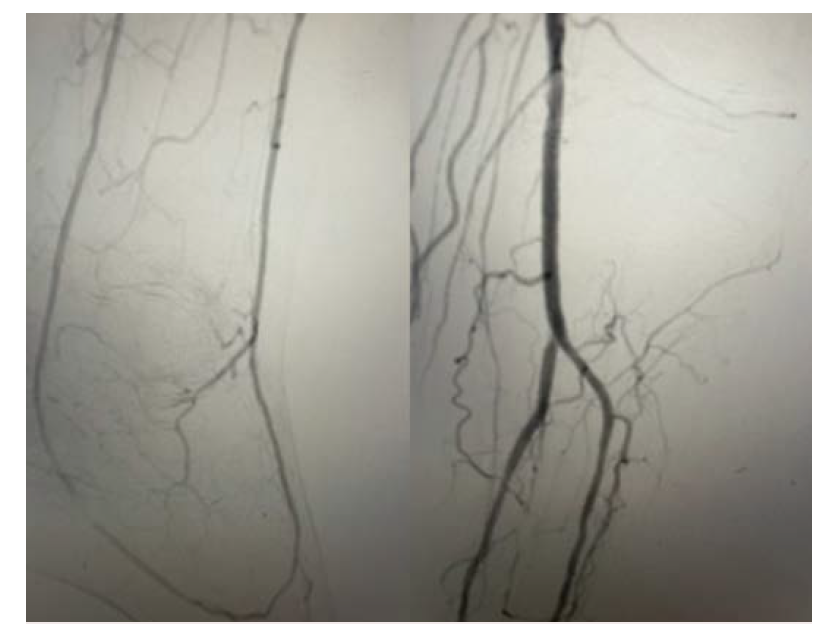

The vascular access will depend on the complexity of the disease as well as the approach. Usually, an antegrade approach is attempted through the common femoral artery, and a 5 to 6 Fr sheath can be inserted. A 6 Fr sheath allows flexibility in using 2 wires with support catheters simultaneously for complex occlusive disease. After vascular access, angiography is performed to evaluate anatomy and disease. Navigation and wiring through calcified occlusions could become challenging. An initial 0.018" support catheter can be attempted, with advancement with a 0.014" wire. The 0.018" support catheter allows more flexibility for wire exchanges and is better for selective angiography. The support catheter can be exchanged for a 0.014" system when traversing the plantar arch. Depending on stenosis severity, calcifications and tortuosity may require different wires to approach and cross stenosis. Our initial wire is often the Regalia (Asahi Intecc), which offers excellent torqueabilty, steerability, and tip resilience. A double bend is helpful to traverse the plantar arch. A wire escalation strategy can then be attempted if initial attempts are unsuccessful (Figure 3).

If antegrade wire escalation fails, a retrograde true lumen crossing approach could be attempted. Again, operator familiarity with wiring and wire escalation is essential. If the stenosis is not crossed, a possible controlled antegrade and retrograde tracking approach would be another option. A retrograde approach through the distal transmetatarsal access could be pursued with challenging cases (Figure 4).

In Figure 5 and Figure 6 we illustrate a case where PAR was performed and the arch was utilized for a retrograde crossing of a flush occlusion of the posterior tibial artery. The patient in our case was referred for CLTI with nonhealing wounds in the toes and heel. The anterior tibial artery was recanalized during the initial procedure using laser atherectomy and angioplasty. Then using an antegrade approach, the anterior tibial artery was wired into the dorsalis pedis, across the arch, and retrograde up the posterior tibial artery into the tibioperoneal trunk and externalized in the popliteal artery. This allowed for recanalization of the anterior and posterior tibial artery with a complete plantar arch on the final angiogram, leading to wound healing.